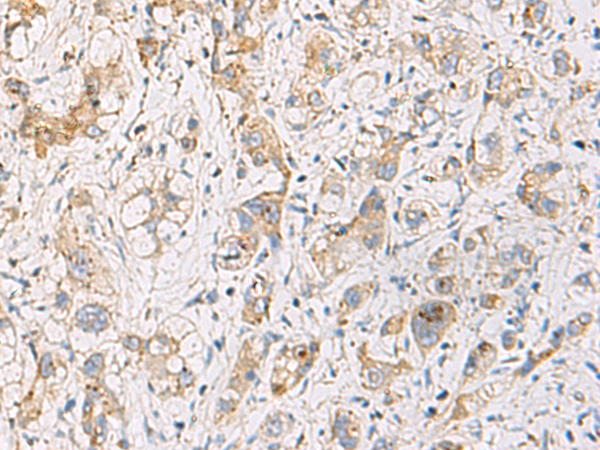

IHC positive control: |

Human liver cancer and Human cervical cancer |

IHC Recommend dilution: |

100-200 |